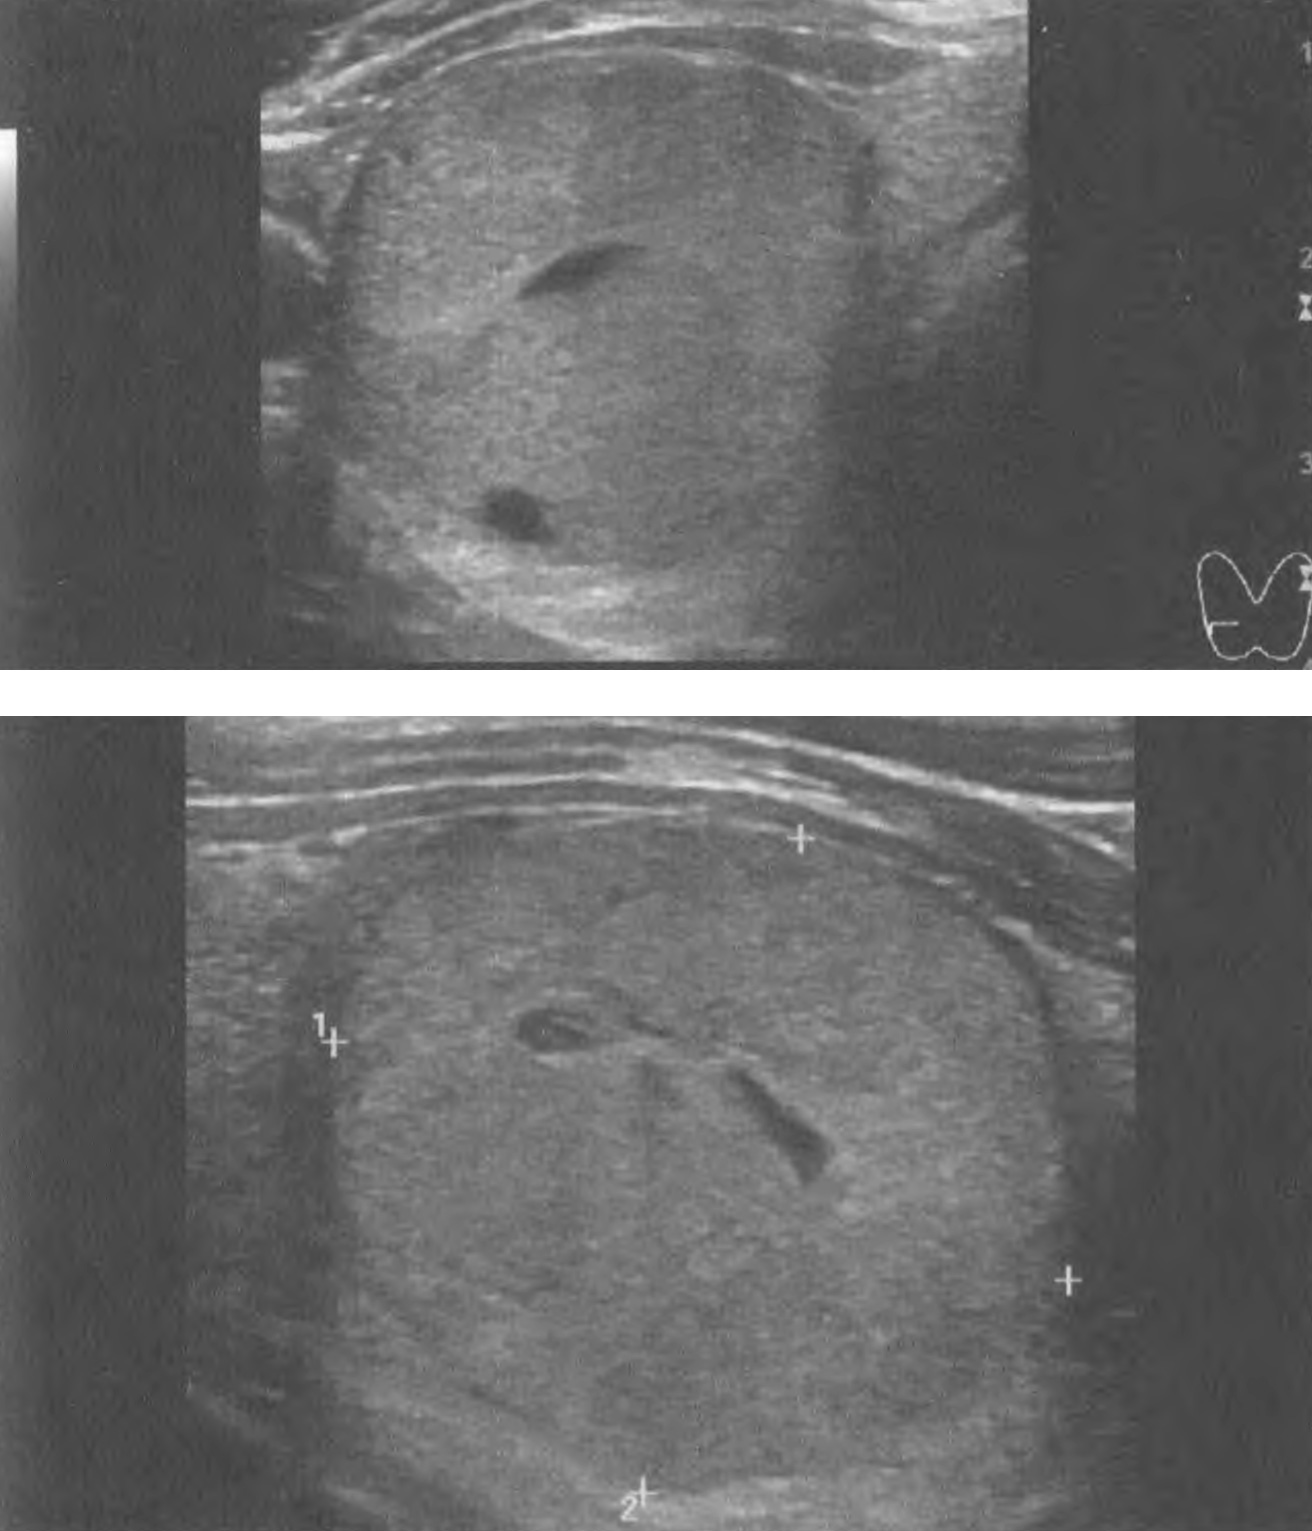

Впрочем, моя зрительная оценка УЗ-примеров (снимков), представленных авторами этого исследования и при которых были допущены ошибки специалистами, быстро выявила признаки рака и доброкачественности, совпавшие с реальностью, что указывает, с одной стороны на недостаточный уровень внимания или знаний специалистов, а с другой – подтверждает способности вспомогательного программного обеспечения (рис. 26, 27). В первом случае (рис. 26) по ACR TI-RADS узлу можно присвоить 8 баллов (5 уровень) – ткань (2 балла), гипоэхогенный участок с неровными контурами внутри узла оценивается как гипоэхогенная ткань (2 балла), неравномерная граница (2 балла), периферическая кальцификация (2 балла). Во втором случае (рис. 27) по ACR TI-RADS узлу можно присвоить 3 балла (3 уровень) – ткань (2 балла), изоэхогенность ткани (1 балл); видны признаки микрокистозных элементов узла в виде мелких анэхогенных включений с тонкими дугообразными мало гиперэхогенными элементами по краям (признак уплотнения соединительной ткани).

Рисунок 27. Пример изображения узла ЩЖ из статьи Е. Lee и соавт. В этом случае 4 специалиста (включая 2-х опытных) определили рак узла. При этом, комбинация из 3 CNN указала на доброкачественность, что подтвердилась после ТАБ как аденоматозная гиперплазия.